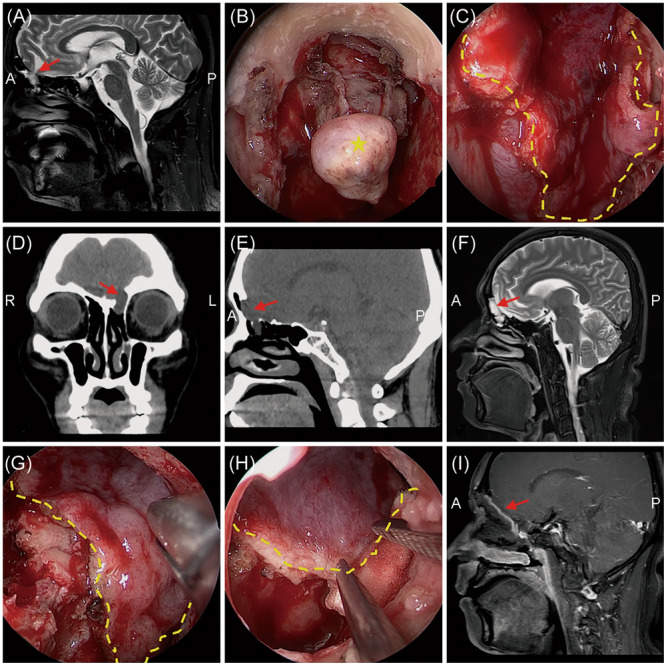

Results: A total of 94 patients with traumatic and 49 patients with nontraumatic CSF rhinorrhea were included. The prevalence of meningitis was significantly higher in traumatic CSF rhinorrhea patients (p = 0.012). Multifocal defects were more frequent in the traumatic group, while sphenoidal defects were significantly correlated with nontraumatic CSF rhinorrhea. Frontal defects were commonly identified in CSF rhinorrhea patients with meningitis than in those without, though no statistical significance was reported. Multivariate logistic regression revealed that male sex, iatrogenic traumatic CSF leak, and pneumonitis are independent factors for development of meningitis. An endoscopic approach combined with an external incision was performed in one patient and 24 patients in nontraumatic and traumatic groups, respectively (p = 0.001). Combined vascularized grafts were more commonly used in patients with traumatic CSF rhinorrhea (p < 0.05). No statistical difference in the success rate (100% vs. 97.9%) was documented between the two groups.

Conclusions: Multifocal defects and meningitis were more prevalent in traumatic CSF rhinorrhea patients, leading to increased complexity in treatment management. Iatrogenic rather than accidental traumatic CSF rhinorrhea is an independent risk factor for development of meningitis. The endoscopic combined coronal extradural approach, in conjunction with various vascularized flaps, can effectively supplement skull base reconstruction, especially for complex traumatic CSF rhinorrhea.